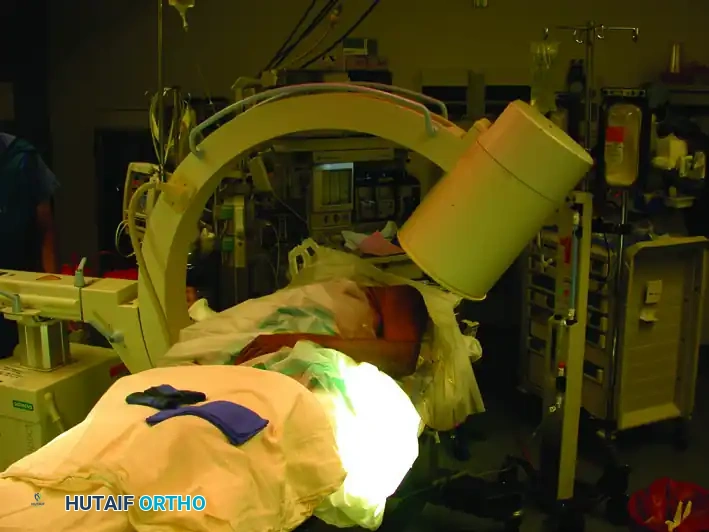

C-Arm Positioning

Place the image intensifier (C-arm) unit on the opposite side of the table from the surgeon. The monitor should be placed at the foot of the bed or across from the surgeon for direct line-of-sight.

The mobility of the C-arm is critical for obtaining orthogonal views without moving the patient's injured extremity:

* Anteroposterior (AP) View: Rolling the C-arm unit back away from the patient allows an adequate AP view of the shoulder and humerus.

* Lateral View: Rolling the unit forward over the patient allows an adequate lateral (scapular Y) view.

Image demonstrating the C-arm rolled back to obtain the Anteroposterior (AP) view.

Image demonstrating the C-arm rolled forward to obtain the Lateral view of the shoulder and humerus.

Composite view: Placement of the image intensifier for intramedullary nailing. Rolling the unit back allows the AP view, whereas rolling it forward allows the lateral view.